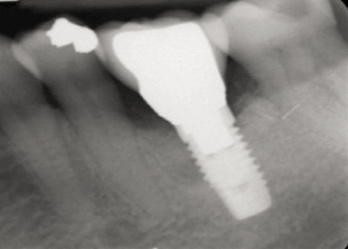

28. Seventeen-month post-treatment radiograph demonstrating bone close to the implant approximation and almost complete osseous fill of the original infrabony defect.

Figure 28

The resolution of the inflammatory aspect of the peri-implantitis lesion (Figure 26) was evidenced by 3-mm pocketing and an absence of bleeding upon probing. A 17-month follow-up (Figure 27) demonstrated resolution of the mucogingival problem, as evidenced by a deepened buccal vestibule, a zone of keratinized gingiva, and correction of the recession. A 17-month post-treatment radiograph (Figure 28) showed bone fill with elimination of the infrabony component of the lesion. Even with the close bone-to-implant approximation evident, a claim of osseous regeneration cannot be validated without histologic verification.

This case report supports this finding as meticulous burnishing of the implant surface with a cotton pellet soaked with sterile saline, along with copious irrigation with a 50:50 hydrogen peroxide-to-water solution, seems to have reduced the bacterial concentration on the implant surface to a level that allowed for almost complete radiographic osseous fill of the vertical component of the infrabony defect. Other readily available antiseptics with a high level of cytotoxicity such as sodium hypochlorite and povidone iodine have also been shown to be efficacious in this regard.32